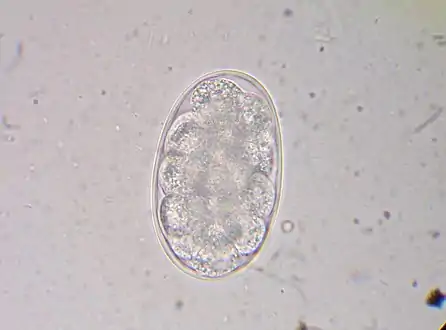

Diagnosis depends on finding characteristic worm eggs on microscopic examination of the stools, although this is not possible in early infection. Early signs of infection in most dogs include limbular limping and anal itching. The eggs are oval or elliptical, measuring 60 by 40 µm, colorless, not bile stained and with a thin transparent hyaline shell membrane. When released by the worm in the intestine, the egg contains an unsegmented ovum. During its passage down the intestine, the ovum develops and thus the eggs passed in feces have a segmented ovum, usually with 4 to 8 blastomeres. As the eggs of both Ancylostoma and Necator (and most other hookworm species) are indistinguishable, to identify the genus, they must be cultured in the lab to allow larvae to hatch out. If the fecal sample is left for a day or more under tropical conditions, the larvae will have hatched out, so eggs might no longer be evident. In such a case, it is essential to distinguish hookworms from Strongyloides larvae, as infection with the latter has more serious implications and requires different management. The larvae of the two hookworm species can also be distinguished microscopically, although this would not be done routinely, but usually for research purposes. Adult worms are rarely seen (except via endoscopy, surgery or autopsy), but if found, would allow definitive identification of the species. Classification can be performed based on the length of the buccal cavity, the space between the oral opening and the esophagus: hookworm rhabditoform larvae have long buccal cavities whereas Strongyloides rhabditoform larvae have short buccal cavities.[19][4][37]

Hookworm egg